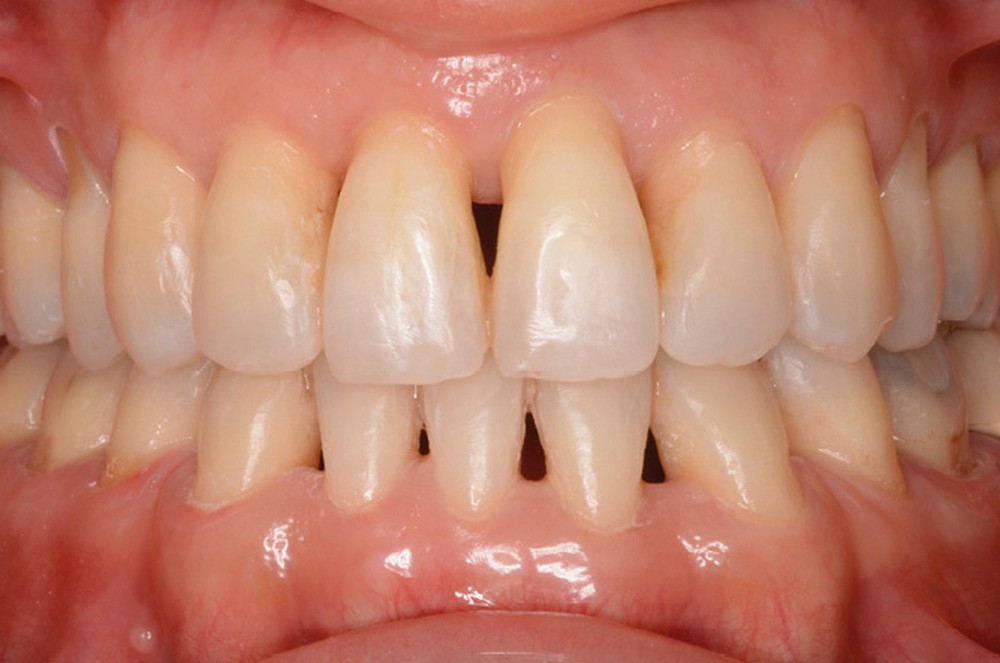

Mme J. présente une face longue, un profil droit avec un angle naso-labial fermé, une birétrocheilie et un menton bien dessiné. La ligne du sourire est basse, avec un sourire denté exposant peu les dents maxillaires, mais avec un parallélisme entre la lèvre inférieure et les bords libres des incisives maxillaires assez harmonieux.

Sur le plan dentaire, la patiente est en classe III droite et gauche, canine et molaire de 6 mm, avec une occlusion inversée antérieure localisée à 11, 12 et 22. Elle présente une dysharmonie dents-arcades sévère, une agénésie d’une incisive mandibulaire est à signaler, et les troisièmes molaires ont été extraites à l’âge de 21 ans.

De plus, nous souhaitons, avec la patiente, corriger son encombrement dentaire afin d’améliorer le pronostic parodontal et l’esthétique du sourire.